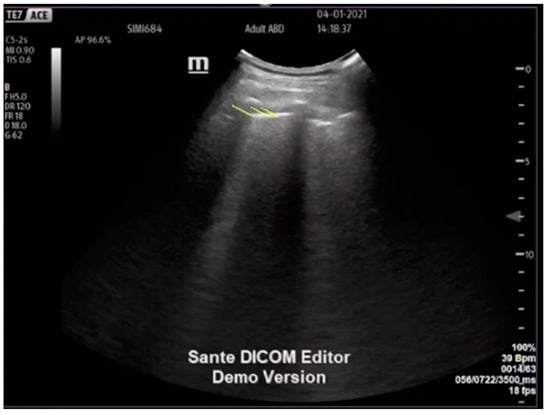

2.2. Collection of Ultrasound Clips

2.3. Classifying Patient Groups